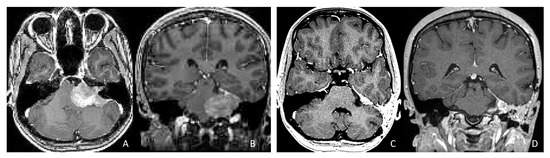

Objectives: Atypical teratoid/rhabdoid tumors (ATRTs) are rare, malignant central nervous system (CNS) neoplasms that predominantly affect infants and young children. While ATRT arises throughout the CNS, its extracranial counterpart, malignant rhabdoid tumor, occurs in other organs. A single-institutional cohort is reviewed to map anatomic distribution of pediatric ATRTs and to integrate a literature review to contextualize ATRT histogenesis from anatomical and embryological perspectives. Methods: A retrospective review was conducted on a cohort of 50 pediatric patients with ATRT treated over 20 years. Demographic, surgical, and neuroimaging data were correlated to define tumor location, extent, and compartmental involvement. A focused literature review synthesized molecular subclassifications and proposed cells of origin/cytogenesis. Results: Of the 50 ATRTs, 18 (36%) were infratentorial, 15 (30%) supratentorial, 11 (22%) in the pineal region, and 6 (12%) in the spinal compartment. Among infratentorial tumors, 10 were centered in the fourth ventricle, with or without extension into the cerebellopontine angle (CPA) cistern; the remainder arose in the CPA. Among ATRTs of the cerebral hemispheres, 3 showed bi-hemispheric involvement crossing the falx cerebri. ATRTs of the pineal region predominantly originated from the superior medullary velum. These topographic data were corelated with embryological and molecular information available in the literature. Conclusions: ATRTs arise across diverse neuroanatomical compartments—including intraparenchymal, intraventricular, extra-axial, and extradural sites—underscoring biological heterogeneity. Inactivation of SMARCB1 is the defining molecular event and principal oncogenic driver, although the upstream mechanisms precipitating these alterations remain incompletely resolved. Molecular subgroups—ATRT-TYR, ATRT-SHH, and ATRT-MYC—display distinct age distributions and anatomic predilections, implicating developmental context in tumor initiation. The characteristic cellular admixture of rhabdoid cells with mesenchymal and/or epithelial differentiation, together with intra- and extra-axial and occasional extradural presentations, supports a model in which at least a subset of ATRTs may originate from neural crest-derived lineages, despite little or no neural crest contribution to brain parenchyma development. Neural plate border progenitors with bipotent features represent a plausible intraparenchymal cell of origin. Definitive resolution of these origins and the mechanisms of SMARCB1 disruption will require integrated approaches. Further investigations are warranted to clarify these mechanisms.